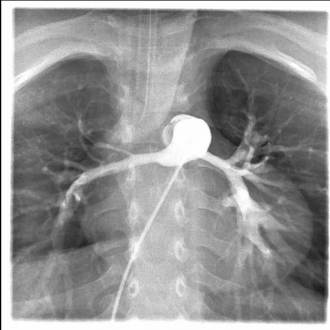

両側BTシャント術後(他院より紹介時の状態)

肺動脈形成後

IPAS後

Fontan手術後